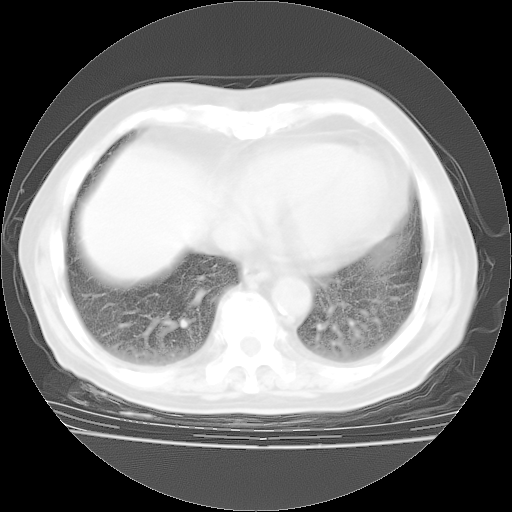

4月28日肺部CT——再次出现类似去年5月9日——透光度降低,“间质性”改变。

4月28日肺部CT——再次出现类似去年5月9日——磨玻璃样、间有“粟粒样”改变。

4月28日肺部CT

个人阅读4.14日肺部CT平扫:纵隔窗无异常,但肺窗示:双下肺内、后基底段有片絮状侵润影,部位以后基底段为著,以间质改变为主,呈急性肺泡炎征像,和首次住院影像学有相似之处。仅是个人读片,明日请相关专家再读片哈。其它建议同上。

1、108#的是4月14日的胸部CT(发此贴时还没看着28日的CT)。14日的胸部CT其实已经出现改变(如108#所述),个人认为28日的胸部CT除纵膈窗疑似有双侧胸膜增厚或少量胸积液(可行胸部B超明确)外,与4月14日对照病变有所加重;2、已经给予“异烟肼、利福平、乙胺丁醇”抗痨治疗?如果是,甲强龙80mg可缓慢减量;如果环磷酰胺已停用,暂不使用;3、中性粒细胞92%,明显升高,目前体温情况?注意合并细菌感染可能,使用左氧氟沙星情况下,是否联用B-内酰胺类抗菌药物?另外是查免疫全套非风湿全套。

今请临免主任会诊后认为:4月14日胸部CT已有双下肺间质性改变。患者病情复发多系激素减量过快不正规所致。目前甲强龙80mg/日,一周后酌情开始减量,不易过快。环磷酰胺若已停用,暂不使用。他同意目前抗菌药物使用,但应考虑是否加用B-内酰胺类抗菌药物(中性细胞明显增高);2、结核复发目前依据不足;3、若免疫全套各项指标正常,考虑多系特发性肺间质炎可能大。4、加强支持,并注意保护胃黏膜。

今上午去请教了临免、呼吸主任:1、介绍病史和阅读系列胸部CT一致认为:患者肺结核不考虑,仍为肺间质纤维化,目前处于急性肺泡炎阶段。2、若仍发热,可将甲强龙增至:80mg Bid静滴,同时鉴于中性增高,合并细菌感染可能,继续左氧氟沙星治疗,再联用B-内酰胺抗菌药物,如头孢哌酮--舒巴坦;3、停用抗痨药;4、目前甲强龙每日剂量160mg ,体温正常后再酌情减量;目前暂不用免疫抑制剂;4、不建议使用免疫增强剂等;5、加强支持治疗,鼓励患者进食;5、注意随访肝、肾功及血常规情况;6、因患者目前激素用量较大,加用胃黏膜保护剂,防止消化道出血可能。